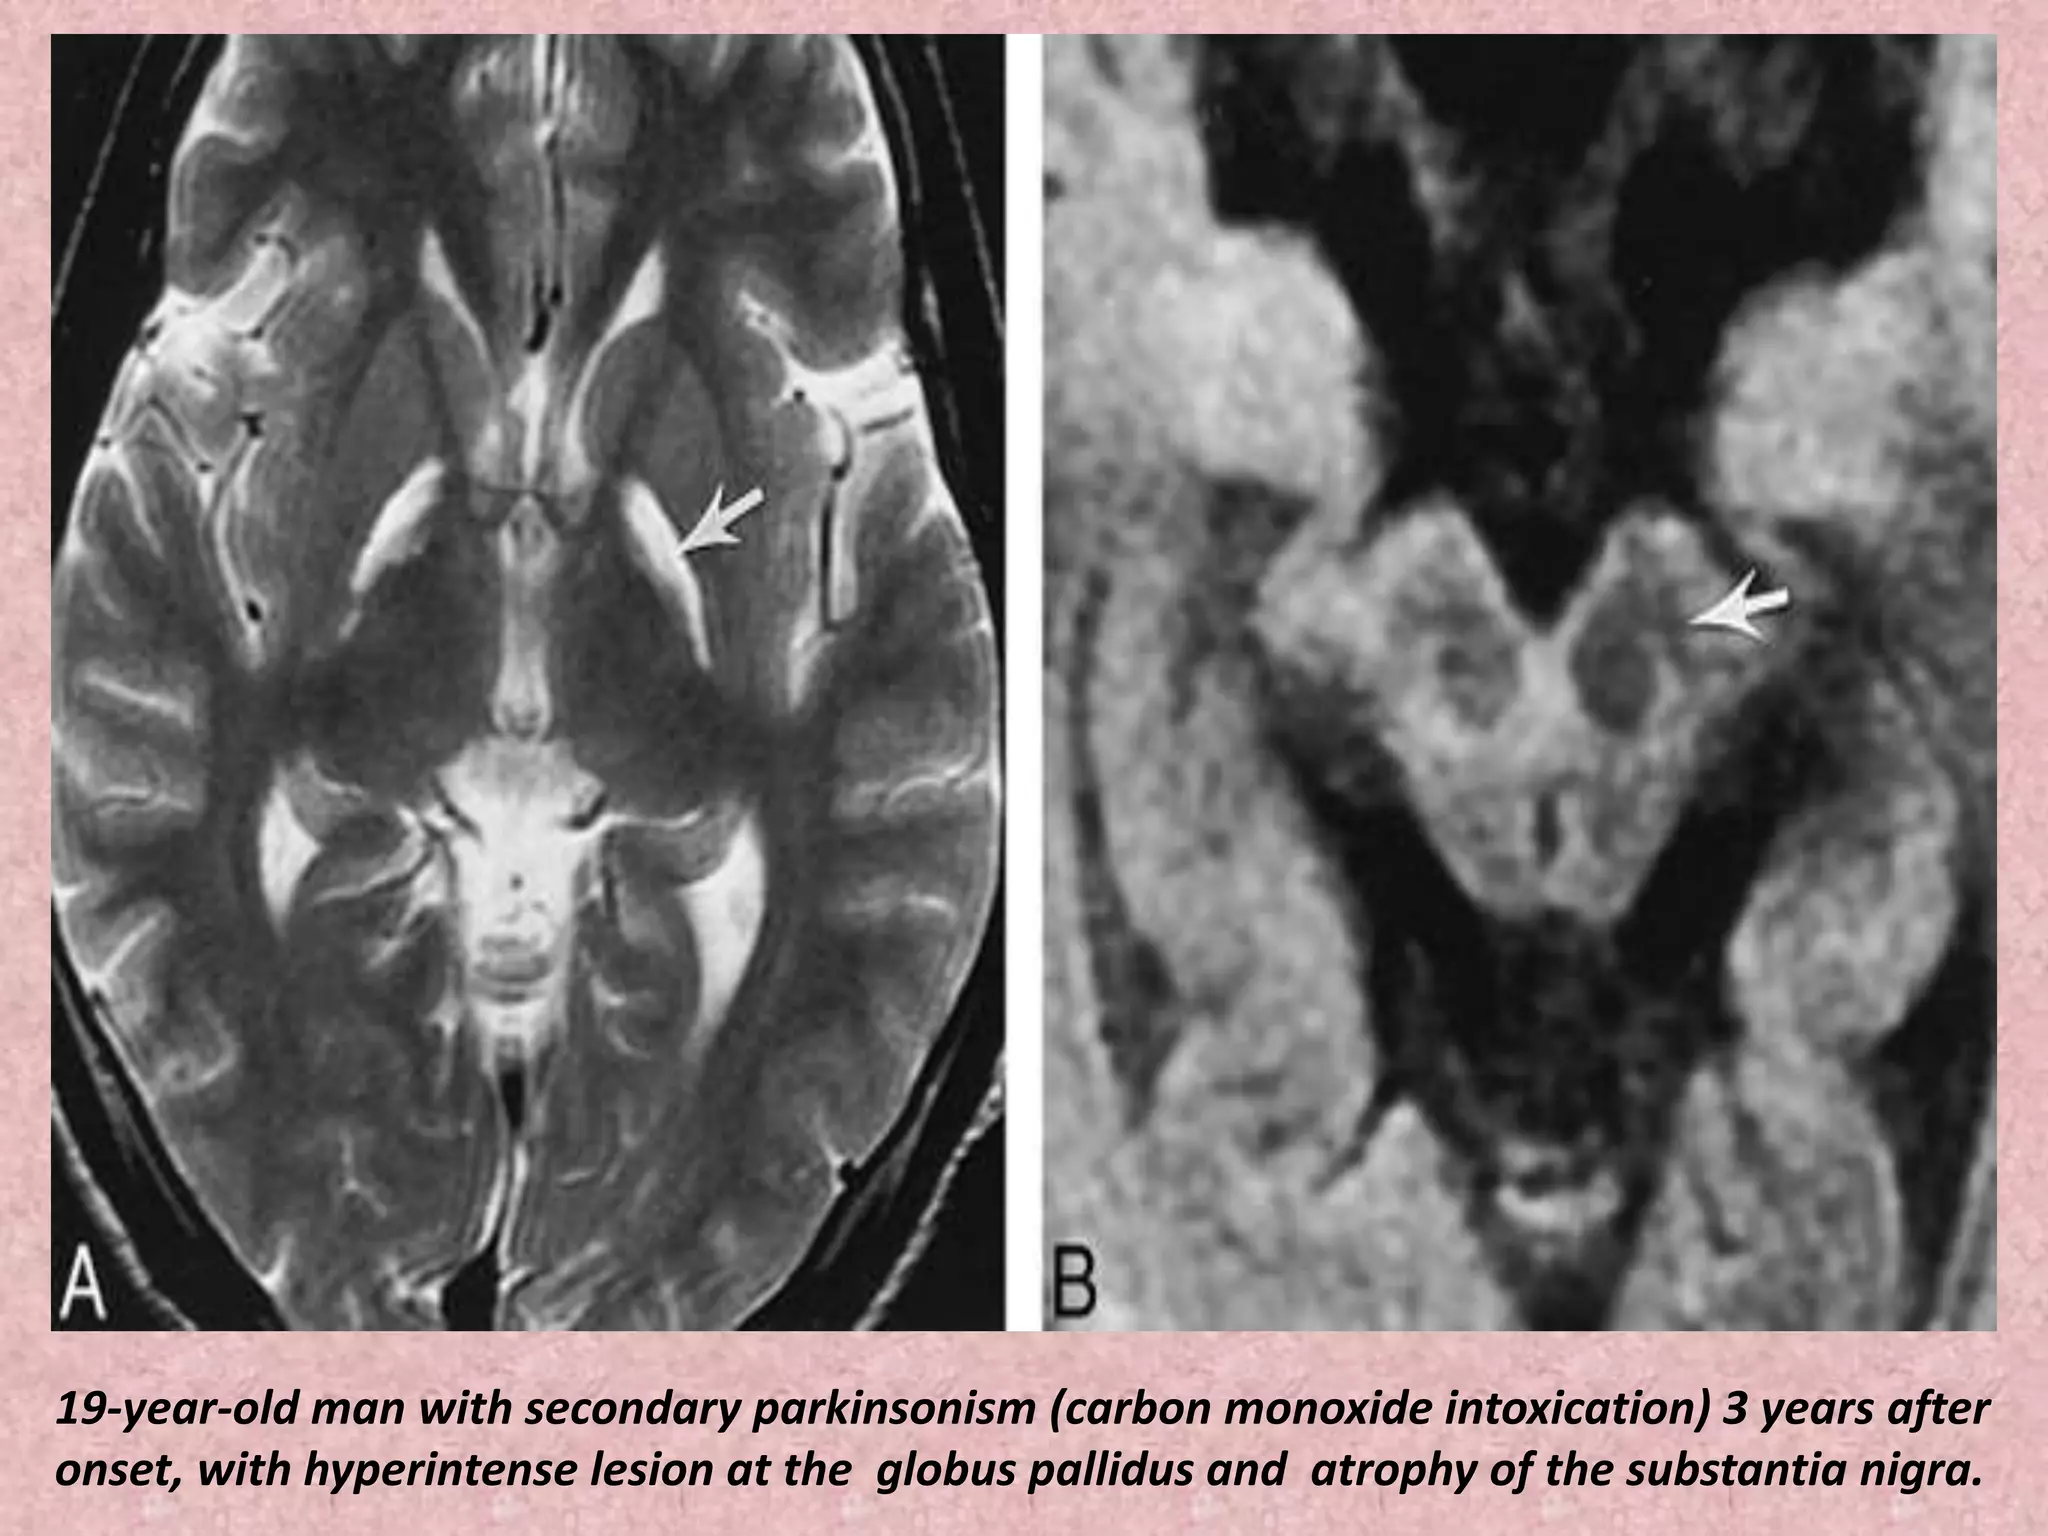

19-year-old man with secondary parkinsonism (carbon monoxide intoxication) 3 years after

onset, with hyperintense lesion at the globus pallidus and atrophy of the substantia nigra.

19-year-old man withsecondary parkinsonism (carbon monoxide intoxication) 3 years after onset, with hyperintense lesion at the globus pallidus and atrophy of the substantia nigra.